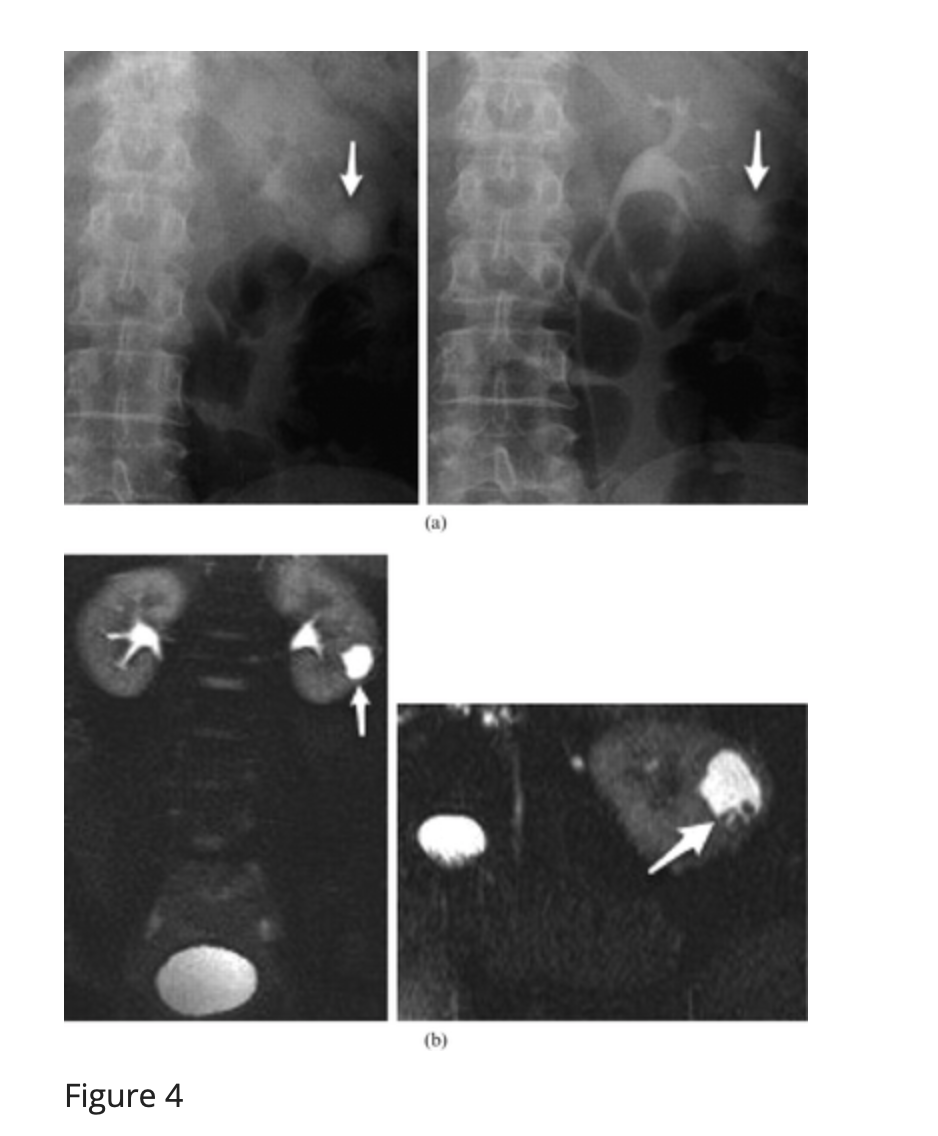

Figure 4

A 50-year-old female with left flank pain. (a) Two radiographs from an intravenous urogram (IVU) study: 20 min (left) and post-micturition (right). The images demonstrate contrast opacifying a lower pole calyceal diverticulum containing numerous calculi (arrow). Further opacification of the diverticulum is evident on the later film (right-hand image; arrow), highlighting the need for delayed images. Note that the infundibulum cannot be seen on either radiograph. (b) Coronal and transverse images from an MR urogram identify the lower pole calyceal diverticulum on the left side (arrow). Multiple areas of low signal are identified within the diverticulum and correspond to calculi (arrow).